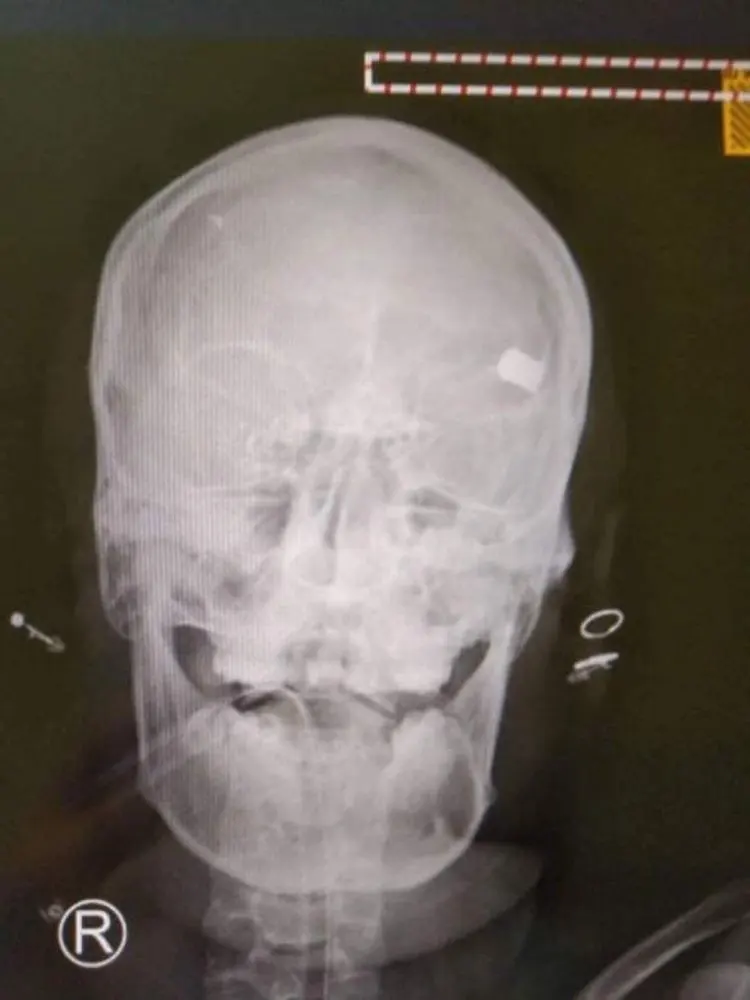

ใช้กระสุนจริงสลายการชุมนุม ตำรวจยิงเสียชีวิต 1 รายที่กรุงเนปิดอว์ เป็นผู้หญิงอายุ 19 ปี

หญิงคนหนึ่งเสียชีวิตที่เนปิดอว์เนื่องจากถูกยิงที่ศีรษะเสียชีวิต 1 รายที่กรุงเนปิดอว์ เป็นผู้หญิงอายุ 19 ปี